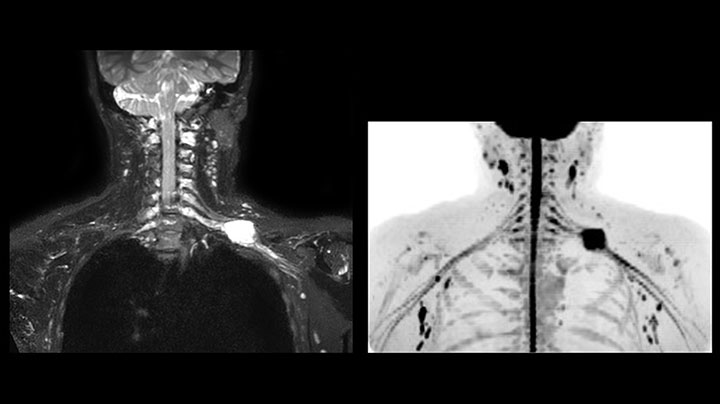

MRI of Pancoast tumor

Although the area between the neck and the top of the lung is one of the most difficult areas for MRI, Prodiva 1.5T images show good quality in this 56-year-old male with Pancoast tumor on the right. mDIXON TFE images shows excellent fat suppression in the neck area and the DWI shows almost no distortion.

MRI of Pancoast tumor

Although the area between the neck and the top of the lung is one of the most difficult areas for MRI, Prodiva 1.5T images show good quality in this 56-year-old male with Pancoast tumor on the right. mDIXON TFE images shows excellent fat suppression in the neck area and the DWI shows almost no distortion.

MR neurography of nerve sheath lesion

This patient is a 43-year-old female with a left supraclavicular nerve sheath tumor. The lesion is well visualized on the STIR VISTA images and on the MR neurography using DWIBS. The exam was performed on Prodiva 1.5T.

Acq voxel size 1.2 x 1.3 x 2.4 mm, Recon voxel size 0.7 x 0.7 x 1.2 mm, dS SENSE factor 2, scan time 5:46 min.